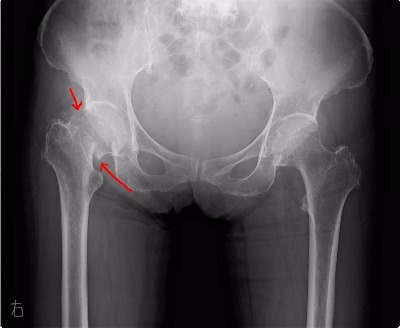

まずレントゲンを撮影して、骨折、ひびが入っていなか検査しました。

レントゲンで右股関節が骨折していました。